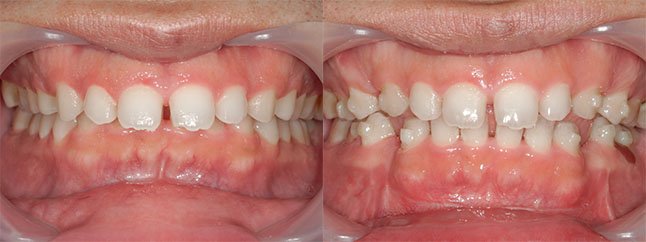

大阪府 19歳 男性

執刀医 辻和志

【治療内容】上下セットバック…上のアゴと下のアゴの両方が前に出ていた為、上下のアゴの骨を切って後ろに下げました。

【費用】上下セットバック 2,307,800円(税込)

【リスク】全身麻酔で行うため全身の健康状態が悪い方は行うことができません。また、手術当日は安静にしていただく必要があります。